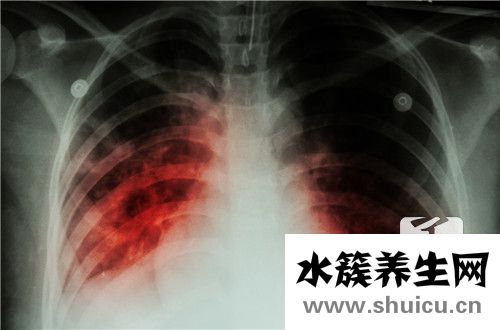

?右肺鈣化是肝實質肺細胞炎癥的陰影,通常與肝膽結石有關,并且肺血管陰影和結核鈣化的發生也可引起肺鈣化,因此應及時治療患者。 不會傳染,可以通過組織修復來改善。 對于右肺鈣化的癥狀,您可以了解以...